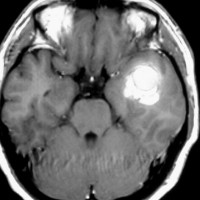

側頭葉てんかんを止めるために,開頭手術をして血管腫を取り除きました.術後のMRIです。一番右のT2starという特殊なMRIでよくわかるように鉄の沈着は残っているので黒く映るものがあります。でもこれは血管腫ではありませんのでこのままにしておきます。この患者さんの場合は,一緒に扁桃体を摘出すること (amygdalectomy) でてんかん発作は治りました。